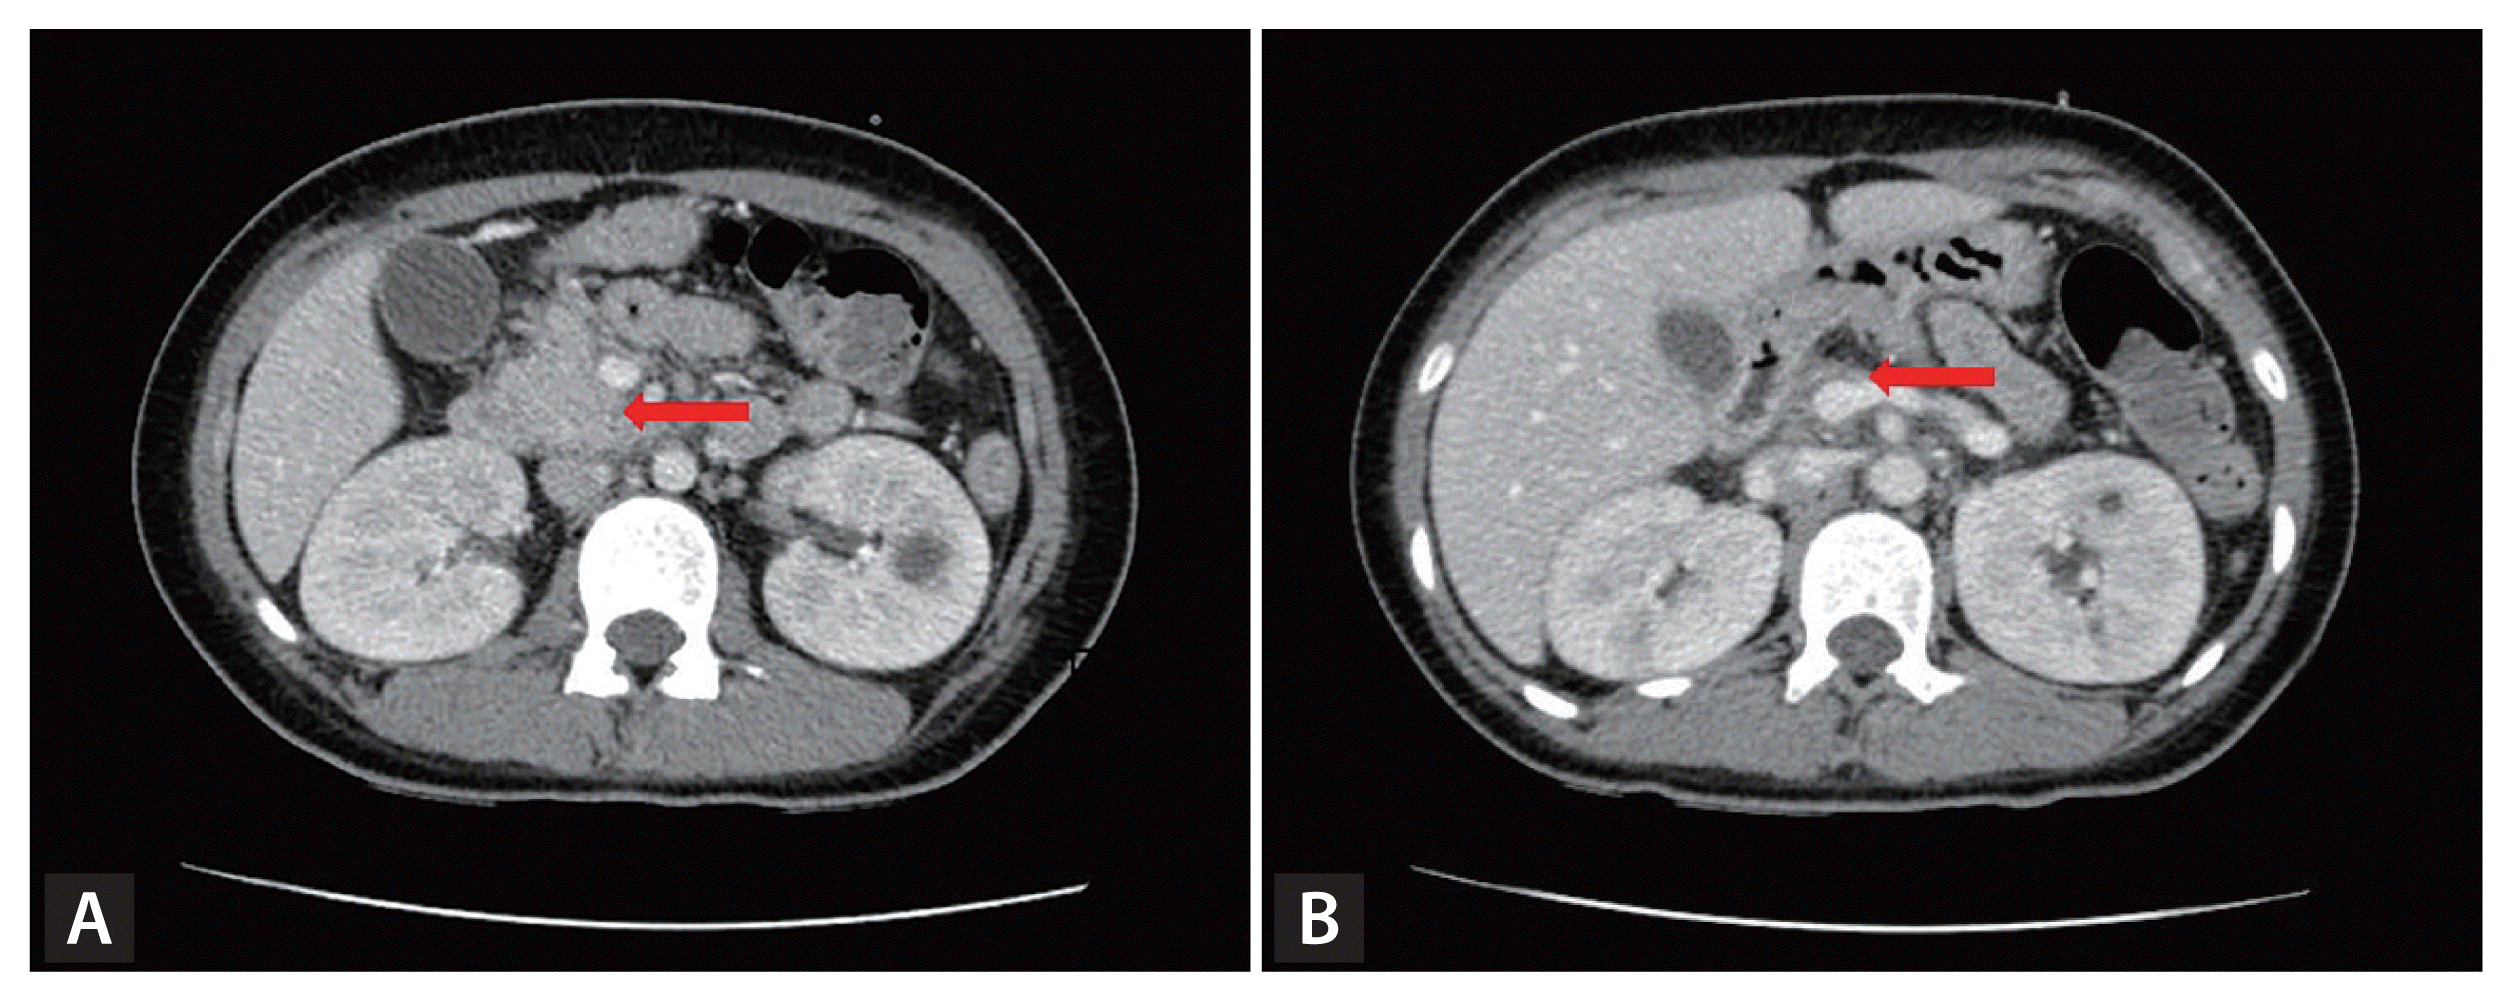

A 14-year-old girl without any previous disease presented to us with abdominal pain and vomiting. Her blood pressure and body temperature were 125/81 mmHg and 37.1°C, respectively. The laboratory findings were as follows: white blood cell count 27,530 × 109/L, hemoglobin 11.7 g/dL, platelet count 408 × 109/L, arterial blood gas analysis (pH 6.906, HCO3 1.7 mEq/L, anion gap 37.3), serum glucose 421 mg/dL, hemoglobin A1c 9.7%, total cholesterol 500 mg/dL, triglyceride 2,051 mg/dL, high-density lipoprotein cholesterol 16 mg/dL, low-density lipoprotein cholesterol 59 mg/dL, amylase 979 U/L, lipase 987.5 IU/L, serum ketone 1.4 mmol/L, serum insulin 9.85 μIU/mL, and C-peptide 0.83 ng/mL. She was diagnosed with diabetic ketoacidosis (DKA) accompanied by acute pancreatitis, and received intensive treatment including hydration, insulin administration, and fasting. Enhanced abdominal computed tomography performed on hospitalization day 14 revealed the absence of pancreatic tissue in the body and tail of the pancreas (Fig. 1). Magnetic resonance cholangiopancreatography was also performed (Fig. 2). Agenesis of the dorsal pancreas (ADP) is an extremely rare congenital anomaly characterized by the absence of the pancreatic neck, body, and tail. Most cases are asymptomatic, and the diagnosis is usually incidental during evaluation for an unrelated issue. Abdominal pain, pancreatitis, weight loss, diabetes, and jaundice are the most commonly associated symptoms and diseases. According to published reports, approximately 50% of patients with ADP also have concomitant hyperglycemia. DKA and severe hypertriglyceridemia complicated by pancreatitis in a patient with ADP has rarely been reported, while ADP initially presenting with DKA accompanied by pancreatitis in early adolescence has never been described earlier.

Figure 2

(A) Magnetic resonance cholangiopancreatography reveals the agenesis of dorsal pancreas. (B) Absence of the dorsal duct of Santorini is observed. In contrast the common bile duct and ventral duct of Wirsung (red arrow) are seen clearly.